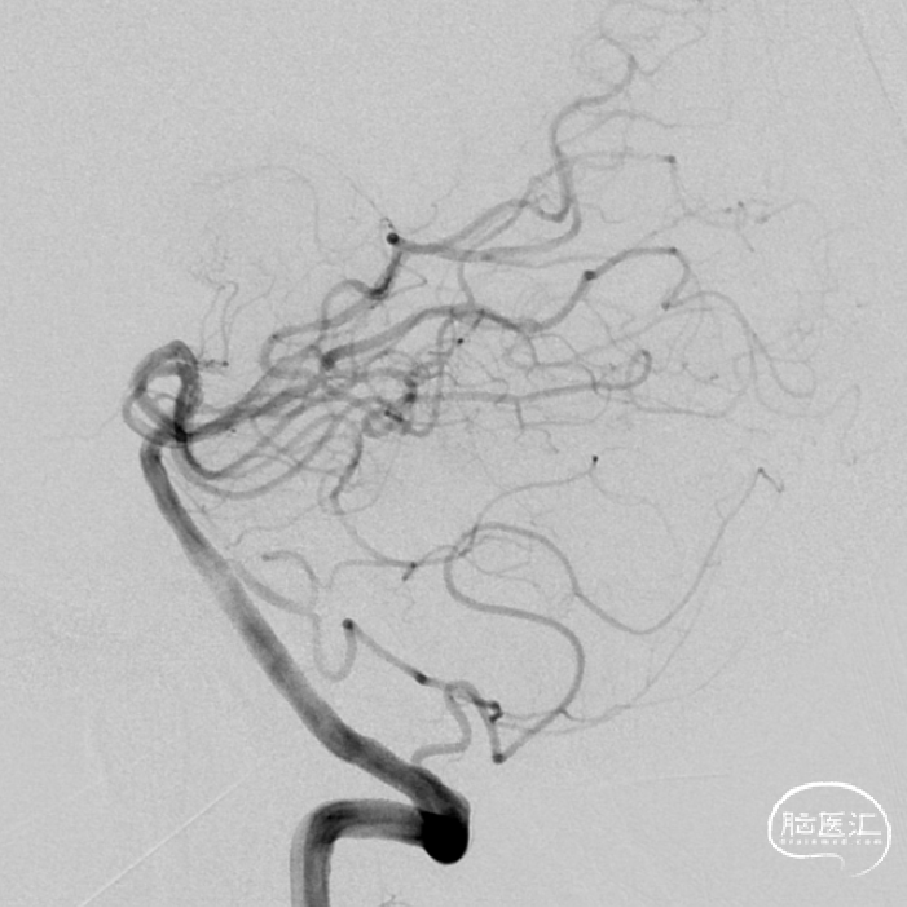

➢DSA(2023.11.10)

R-DAS技术超选右侧颈内,右侧颈内动脉血管迂曲。